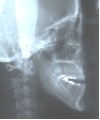

日本矯正歯科学会専門医課題症例(第7症例)

カテゴリー:開咬(overbiteがマイナスのもの)

| 初診時